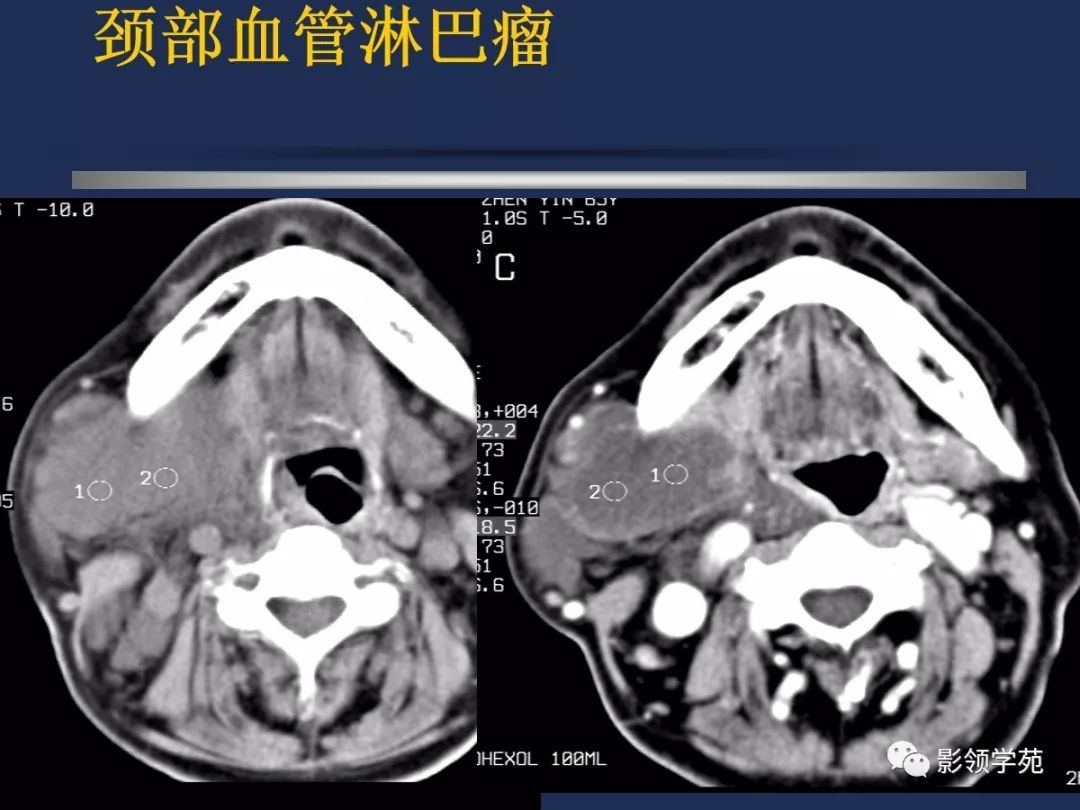

颈部常见疾病影像诊断

- 血管瘤

- 淋巴结肿大性疾病